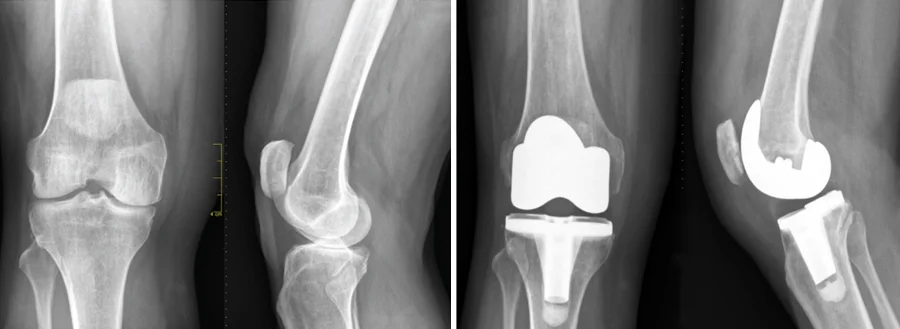

Total Knee Replacement

Dr Randhawa may recommend knee replacement surgery if you have significant arthritis. The joint is not replaced, just the damaged cartilage found at the ends of the bones in your knee.

A knee replacement will resurface a joint with an implant, usually made from metal alloy and polyethylene. Implants help to restore function to the knee and eliminate as much discomfort as possible, all while enabling you to return to an active lifestyle.

X-ray taken after Total Knee Replacement